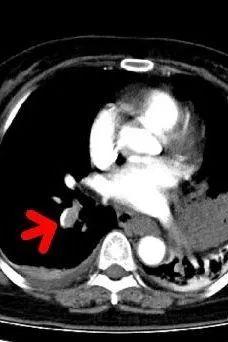

CT检查提示右肺下动脉栓塞,延伸到右肺动脉干